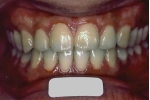

初診時